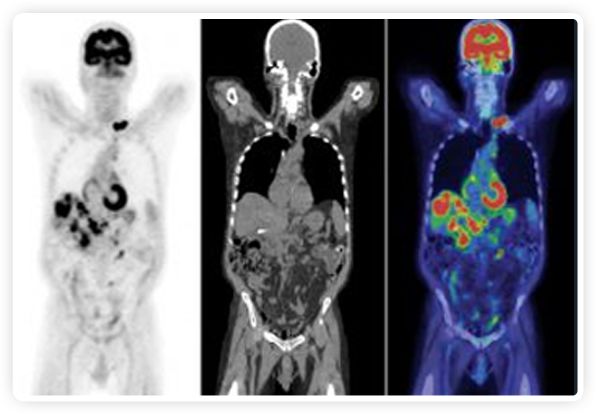

正電子發(fā)射斷層掃描(PET)是癌癥檢測中已建立的成像標準,與其他成像方式相比,PET能提供高靈敏度和特異性的圖像。

到目前為止,放射腫瘤學中(使用的圖像主要是結構性的,而PET圖像可以提供生物學信息。通過使用注射示蹤劑,例如18-FDG,PET可以描繪腫瘤的代謝活性,使其“點亮”。(FDG是用于可視化癌癥代謝的最廣泛使用的示蹤劑。與正常組織相比,腫瘤細胞保留更高水平的FDG。)不同的PET示蹤劑可以識別腫瘤的不同生物學特征,例如特定生物標志物抗原(例如,PSMA)或甚至探測免疫系統(tǒng)本身(例如,PDL1表達或活化的T細胞)。